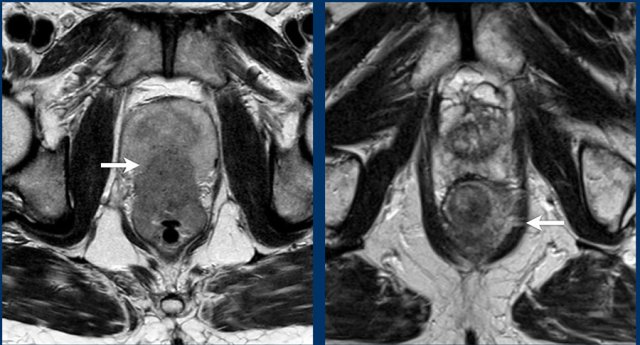

It can be difficult to discern true perirectal tumor invasion in T3 tumors (case A) from desmoplastic stranding in T1-2 tumors (case B), which can be a potential cause of overstaging.

Images

The image on the left shows a tumor with a close relation to the peritoneum and the bladder (white arrow).

However there is no tumor extension beyond the muscularis propria anteriorly and the peritoneum is therefore not invaded.

The image on the right shows definite tumor invasion of the peritoneum (yellow arrow), i.e. a T4a tumor.